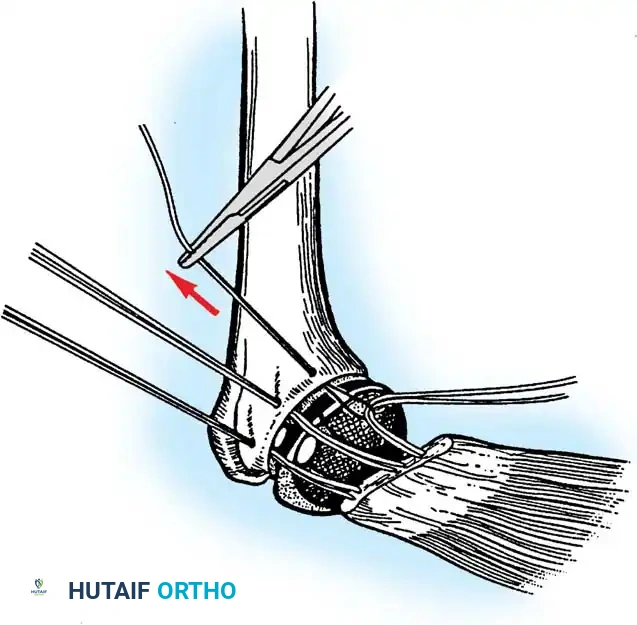

- Ulnar Nerve Management: The ulnar nerve must be identified, mobilized, and protected throughout the procedure. Routine anterior transposition is performed at the conclusion of the case.

- Triceps Management: Several options exist, including a triceps-reflecting approach (Bryan-Morrey), a triceps-splitting approach, or a triceps-sparing approach. The Bryan-Morrey approach involves reflecting the triceps from medial to lateral in continuity with the anconeus and forearm fascia.

4. Closure

The triceps mechanism is meticulously repaired using heavy non-absorbable sutures through drill holes in the proximal ulna. The ulnar nerve is secured in a subcutaneous anterior transposed position, ensuring no fascial bands compress it.